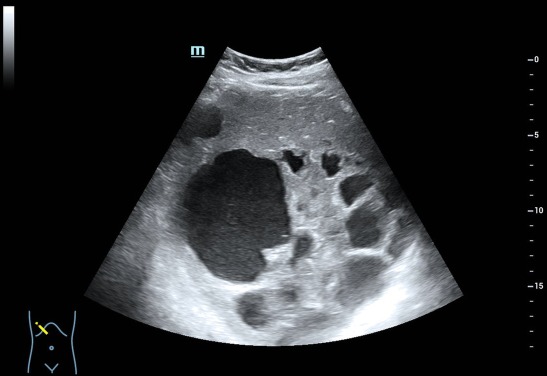

肝脏体积增大,右叶斜径约 19.0cm ,肝内可见多个厚壁无回声,大的位于肝右叶,大小约 15.5cmx13.9cm 的囊实性结节,内可见粗大分隔及壁结节,肝内胆管未见扩张。CDFI: 囊肿周边可见少许血流信号(图 1-5 )。

图 2 去年 8 月肝内可见一巨大囊实性结节,内可见粗大分隔、厚壁及壁结节